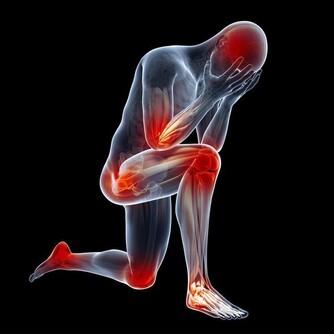

腰痛

很多女性會長期出現腰痛現象,即使是非經期也會出現,這和四種婦科疾病有關。